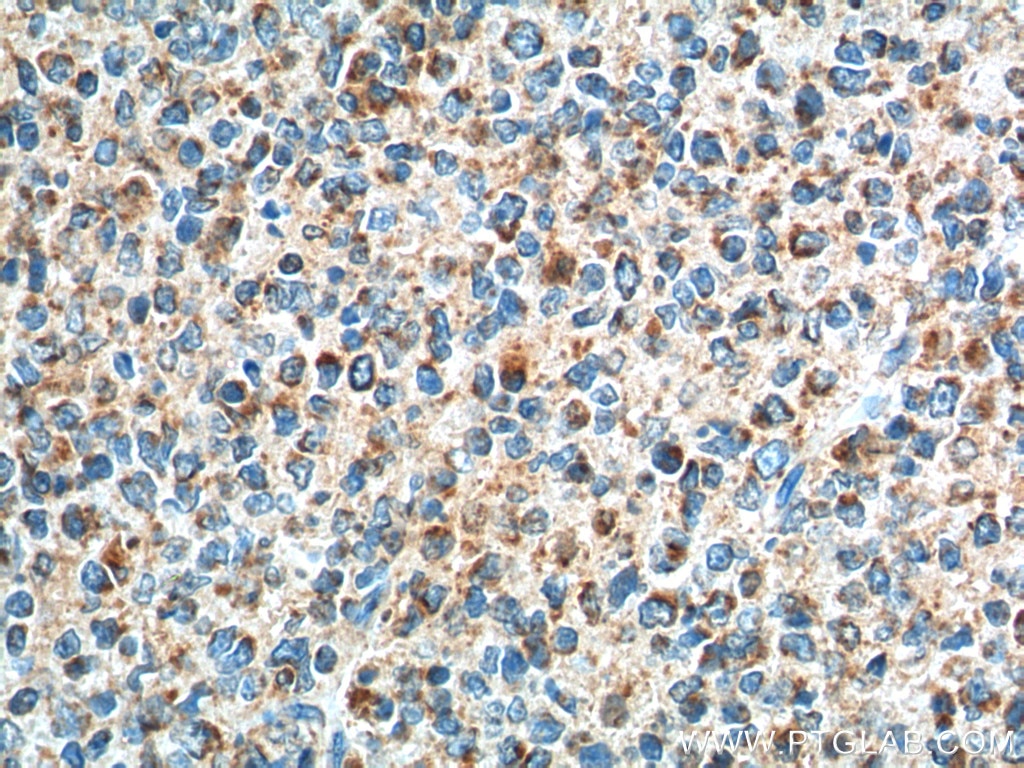

| Positive IHC detected in | human tonsillitis tissue Note: suggested antigen retrieval with TE buffer pH 9.0; (*) Alternatively, antigen retrieval may be performed with citrate buffer pH 6.0 |

20306-1-AP targets GPR65 in IHC, ELISA applications and shows reactivity with human samples.